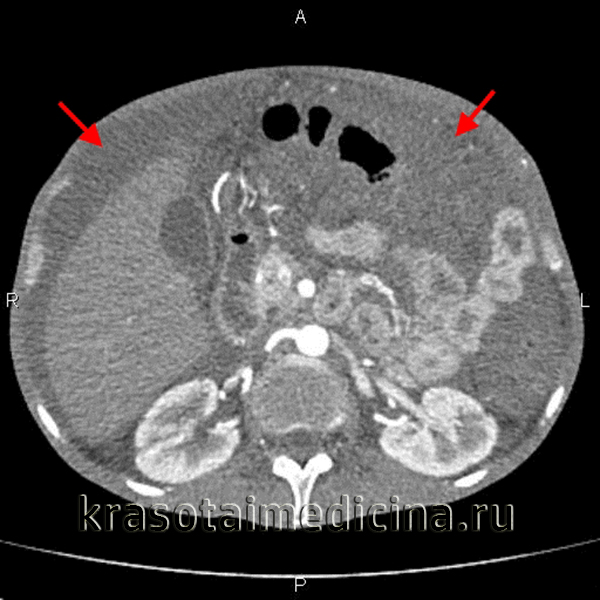

(Слева) На аксиальной Т2 МР томограмме с жироподавлением определяются осумкованные скопления дающей гиперинтенсивный сигнал жидкости. Обратите внимание на отдельно расположенные узлы в асцитической жидкости, отображающие тот факт, что асцит является «злокачественным» и возник в результате метастатического поражения брюшины при первичном раке аппендикса.

(Справа) На аксиальной КТ без контрастного усиления у пациента после трансплантации тонкой кишки определяются уровни «жидкость-жир» в скоплениях жидкости, которые отражают ее хилезную природу — результат утечки лимфы из лимфатических сосудов тонкой кишки.